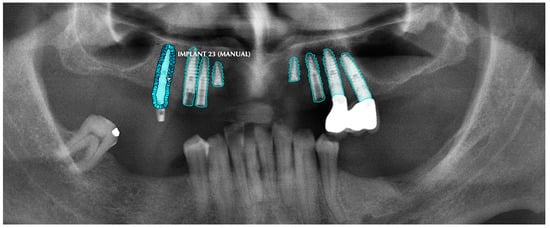

All of the objects mentioned above were segmented by determining their margins by creating points, and the model was trained separately for each of the structures with those segmentations (Figure 1).

Figure 1.

Manual segmentation process of the dental implants. Note the precision for the dental implant’s grove segmentation in order to achieve higher accuracy and DSC.